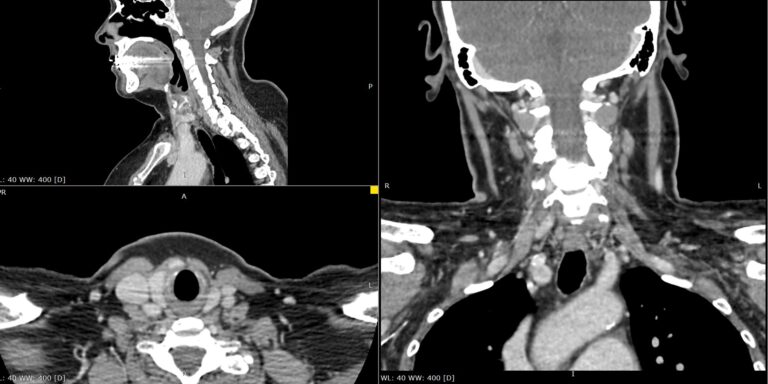

Мультиспиральная компьютерная томография позволяет точно определить размеры и расположение паращитовидных желез, в том числе при атипичном их расположении (загрудинно, в средостении), выявить опухолевые образования, оценить их структуру, степень кровоснабжения, взаимодействие с окружающими тканями.

В клинике «Доступная медицина» данное исследование выполняется по трем различным протоколам (в нативную, раннюю артериальную и позднюю венозную фазы сканирования). Это соответствует современным мировым стандартам, применяемым для наиболее точного определения характера выявленных образований, в частности, позволяет отличить злокачественные опухоли от доброкачественных.

Обследование проводится на мультиспиральном 128-срезовом томографе экспертного класса TOSHIBA AQUILION CXL. Аппарат выполняет послойное сканирование исследуемой области с толщиной среза от 0,5 мм. Увеличенное количество детекторов позволяет максимально сократить время исследования при минимальной лучевой нагрузке на пациента. При этом сканер дает детальную информацию о зоне исследования, а современные компьютерные программы преобразуют полученные данные в 3D-изображения высокого качества.

При отсутствии патологических изменений паращитовидные железы могут быть практически не видны, поэтому для их визуализации обязательно применяется контрастное усиление. Для этого пациенту внутривенно вводится йодсодержащий контрастный препарат. Контрастное вещество быстро распространяется по кровеносной системе и накапливается в патологических очагах, что хорошо видно на снимках КТ. Таким образом, контрастирование помогает выявлять опухоли на начальной стадии развития, когда лечение наиболее эффективно.